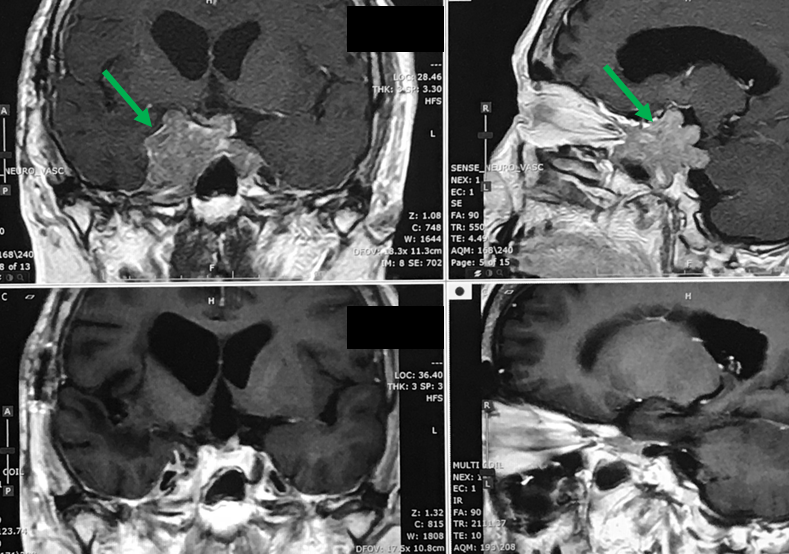

60代の男性に発生した頭蓋底部の髄膜腫です(上段の赤矢印)。手術で摘出できないということで放射線治療のために紹介受診されました。この患者さんの場合、視機能に関する神経が近くにあることから慎重な治療が必要であると考えられました。このため、一回1.8Gyで30回照射する(54Gy/30回照射)という方法で治療しました。現時点での知見では、この方法が視機能温存に関して最も安全かつ治療効果が高いと考えられます。ただ、30回に分けて照射するということは治療に6週間もかかるということを意味しており、このことがこの治療法の欠点とも言えます。しかしながら私どもは安全第一の観点からこの30回に分けての照射を多用しています。治療終了まで6週間かかり、患者さんは遠方からの方が多いので入院で照射する方が多いのですが、外来照射も可能です。下段の写真はノバリスによる治療から21か月後のMRI検査結果です。腫瘍は明らかに縮小しています。

70代の女性に発生した頭蓋底部の髄膜腫です(上段左写真の赤矢印)。手術で摘出できないということで放射線治療のために紹介受診されました。この患者さんも視機能に関する神経が近くにあることから慎重な治療が必要であると考えられました。このため、一回1.8Gyで30回照射する(54Gy/30回照射)という方法で治療しました。下段の写真はノバリスによる治療の際の線量分布を示しています。本例ではHybridArc(ハイブリッドアーク)と呼ばれるIMRTの技術を取り入れた照射を行っています。上段中央は照射5か月後、上段右の写真は治療1年後のMRI検査結果であり、腫瘍は縮小傾向にあります。治療に伴う合併症はみられませんでした。

70代の女性に発生した異形成髄膜腫です(上段左写真の赤矢印)。何度も手術を行いましたが、再発を繰り返すということで放射線治療のために紹介受診されました。この患者さんも視機能に関する神経が近くにあることから一回1.8Gyで30回照射する(54Gy/30回照射)という方法で治療しました。下段の写真はノバリスによる治療の際の線量分布を示しています。本例ではハイブリッドアークと呼ばれるIMRTの技術を取り入れた照射を行っています。上段中央は照射5か月後、上段右の写真は治療1年後のMRI検査結果であり、腫瘍は著明に縮小しています。治療に伴う合併症はみられませんでした。